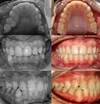

Şeffaf Plaklarla Tedavi, Lingual Ortodontik Tedavi, Şeffaf ve Metal braketlerle Sabit Ortodontik Tedavi, Hareketli / Fonksiyonel Çene Ortopedisi, Ortognatik Cerrahi ve Obstrüktif Uyku Apnesi tedavi uygulamaları yapmaktayım.

Sınıf 3 Malokluzyonlar

Diş Çapraşıklığı

Sınıf 2 Malokluzyonlar

Sınıf 1 Malokluzyonlar